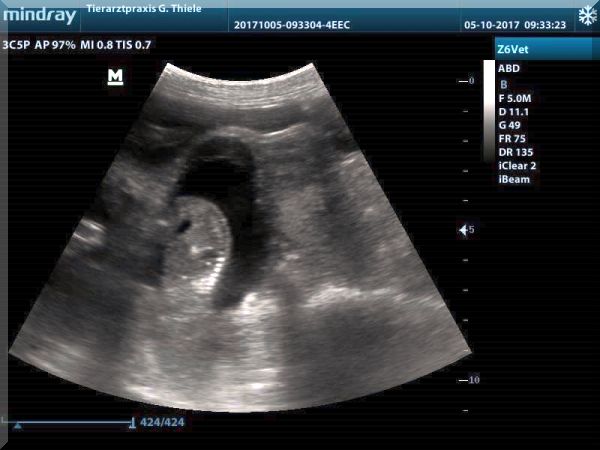

Ultraschall-Bilder von Gloria vom Wieratal

vom 05.10.2017

unser Z-Wurf